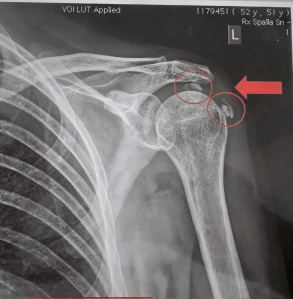

Tendinopatia, doppia calcificazione della cuffia dei rotatori (spalla sx)